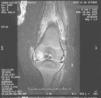

Permaneció ingresado en período neonatal durante 35 días, durante el que presentó enterocolitis necrosante y candidiasis sistémica (2 hemocultivos identificaron Candida albicans, acompañada de candiduria). La candidiasis sistémica se trató durante 21 días con anfotericina B liposómica intravenosa. El hemocultivo de control resultó negativo. En la exploración física se observó peso de 11,8kg; talla de 74,5cm; temperatura corporal de 38°C; frecuencia cardíaca de 130 latidos por minuto, y presión arterial de 123/61. Presentaba dificultad para la movilidad activa y pasiva de la rodilla izquierda (en la flexión), con aumento de temperatura local y tumefacción, sobre todo de la zona superior. La hemoglobina era de 11,2g/dl; el recuento de leucocitos era de 5.420×109/l (3.130×109/l de neutrófilos); el recuento de plaquetas era de 180×109/l, y la proteína C reactiva (PCR) era de 2,1mg/dl. En la ecografía de la rodilla izquierda se apreció un engrosamiento hiperecogénico de la membrana sinovial en la zona suprarrotuliana con líquido ecogénico en la bursa. Se observó una ligera irregularidad de la superficie cortical anterior del fémur distal izquierdo. La ecografía de cadera izquierda resultó normal. En la resonancia magnética (RM) se observó un derrame articular en cantidad moderada con marcado engrosamiento sinovial (en la rodilla izquierda), además de una alteración de la intensidad de señal del cartílago del cóndilo femoral interno, que llegó a contactar con la superficie articular (fig. 1). Se inició tratamiento antibiótico con cefotaxima y cloxacilina, pero el niño continuaba febril y con limitación funcional de la rodilla izquierda.

Resonancia magnética inicial de rodilla izquierda. Derrame articular en cantidad moderada y marcado engrosamiento sinovial. Alteración de la intensidad de señal del cartílago del cóndilo femoral interno izquierdo, que contacta con la superficie articular. Compatible con artritis con afectación femoral.